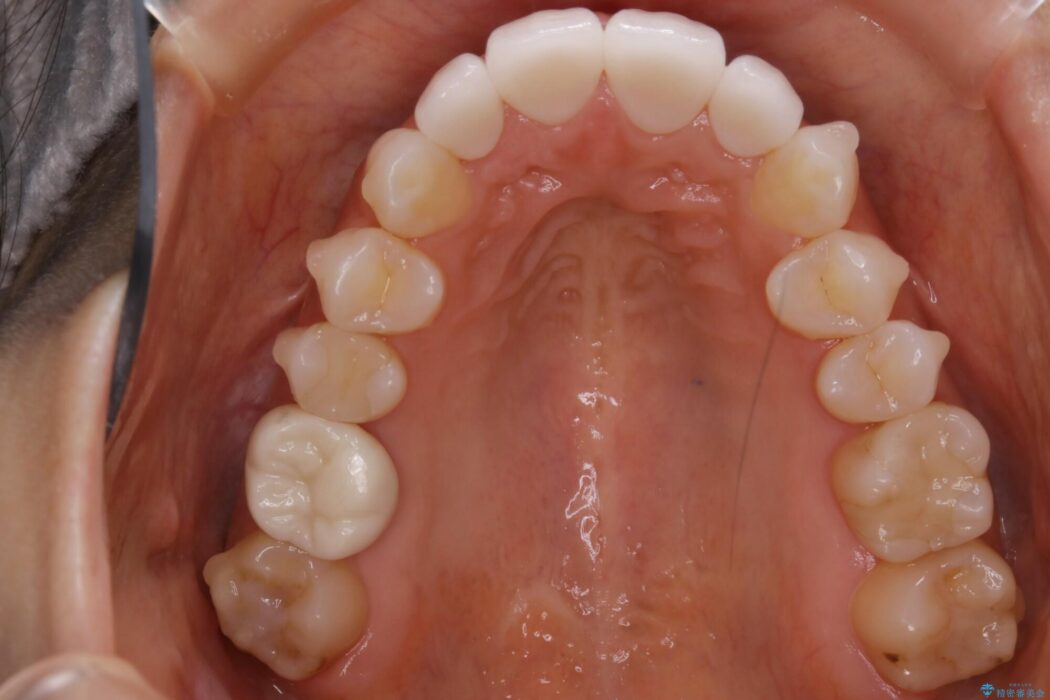

本症例ではセラミッククラウンのかぶせ物をした歯が複数ありました。

セラミック等の被せ物がある場合、それ自体の外形は矯正治療では変えられないため天然歯の移動に影響を与えてしまうことがあります。

加えてインビザラインでの治療上設定されるアタッチメント(歯の表面に付けるプラスチックの突起)が外れやすい場合が多く、歯の移動に対する力が不足する可能性があります。